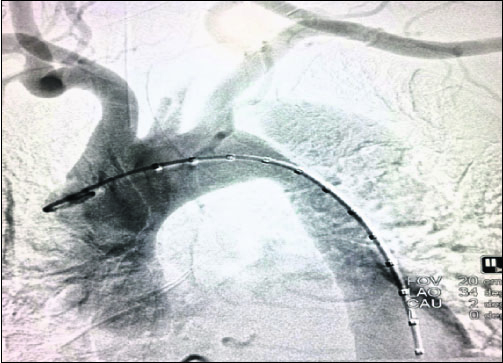

ଭୁବନେଶ୍ୱର, ୩।୨(ବ୍ୟୁରୋ):କିମ୍ସ-ଭୁବନେଶ୍ୱରରେ ହାଇବ୍ରିଡ୍ ଅସ୍ତ୍ରୋପଚାର ସଫଳ ହୋଇଛି। ଓଡ଼ିଶାରେ ପ୍ରଥମଥର ଲାଗି ହାଇବ୍ରିଡ୍ ଅସ୍ତ୍ରୋପଚାର କରାଯାଇଥିବା ସମ୍ପୃକ୍ତ ଡାକ୍ତରମାନେ ଦାବି କରିଛନ୍ତି। ନିକଟରେ କଟକ ଜିଲା ବାଙ୍କୀ ବ୍ଲକ୍ ଅନ୍ତର୍ଗତ ରତାଗଡ଼ ଗ୍ରାମର ୫୦ବର୍ଷ ବୟସ୍କା ସୁଷମା ରଣାଙ୍କ ମୁଖ୍ୟ ରକ୍ତନଳୀରେ ଏହି ଅସ୍ତ୍ରୋପଚାର କରାଯାଇଛି। ପିଠିର ଉପରିଭାଗ ଓ ଛାତିରେ ଅସହ୍ୟ ଯନ୍ତ୍ରଣା ଅନୁଭବ କରିବାରୁ ସେ ଡାକ୍ତରଙ୍କ ସହ ପରାମର୍ଶ କରିଥିଲେ। ବିଭିନ୍ନ ଡାକ୍ତରଖାନାକୁ ଯାଇ ଚିକିତ୍ସିତ ହୋଇଥିଲେ ମଧ୍ୟ କୌଣସି ସୁଫଳ ନ ମିଳିବାରୁ ଶେଷରେ ସୁଷମା ଗତ ୧୮ ତାରିଖରେ କିମ୍ସ ହୃଦ୍ରୋଗ ବିଭାଗ ଡାକ୍ତରଙ୍କ ସହ ପରାମର୍ଶ କରିଥିଲେ। ବିଭିନ୍ନ ପରୀକ୍ଷା ନିରୀକ୍ଷା ପରେ ସୁଷମାଙ୍କ ହୃତ୍ପିଣ୍ଡରୁ ବିଭିନ୍ନ ଅଙ୍ଗ ପ୍ରତ୍ୟଙ୍ଗକୁ ରକ୍ତ ସଞ୍ଚାଳନ ହେଉଥିବା ମୁଖ୍ୟ ରକ୍ତନଳୀ ଫାଟିଯାଇ ଇଣ୍ଟରନାଲ୍ ବ୍ଲିଡିଂ ହେଉଥିବା ଜଣାପଡ଼ିଥିଲା। ତେଣୁ ତୁରନ୍ତ ତାଙ୍କର ହାଇବ୍ରିଡ୍ ଅସ୍ତ୍ରୋପଚାର ପାଇଁ ଡାକ୍ତର ନିଷ୍ପତ୍ତି ନେଇଥିଲେ। ପ୍ରଥମେ କିମ୍ସର କାର୍ଡିଓଥୋରାସିସ୍ ଓ ଭାସ୍କୁଲାର ସର୍ଜରି (ସିଟିଭିଏସ୍) ବିଶେଷଜ୍ଞ ଡା. ଏ. ଶାରଦା ଏବଂ ଡା. ଚନ୍ଦନ କୁମାର ରାୟମହାପାତ୍ରଙ୍କ ନେତୃତ୍ୱରେ ତାଙ୍କର ବାଇପାସ୍ ଅସ୍ତ୍ରୋପଚାର କରାଯାଇଥିଲା। ଏଥିରେ ମୁଖ୍ୟ ରକ୍ତନଳୀରୁ ବାମ ହାତ ଓ ମସ୍ତିଷ୍କକୁ ରକ୍ତ ସଞ୍ଚାଳନ କରୁଥିବା ରକ୍ତନଳୀ ସହ ଦୁଇଟି ନଳୀ ସଂଯୋଗ କରାଯାଇଥିଲା। ପରେ ହୃଦ୍ରୋଗ ବିଶେଷଜ୍ଞ ଡା. ଅନୁପମ ଜେନାଙ୍କ ଦ୍ୱାରା ଷ୍ଟେଣ୍ଟି କରାଯାଇ ମୁଖ୍ୟ ରକ୍ତନଳୀର ଫାଟି ଯାଇଥିବା ସ୍ଥାନକୁ ବନ୍ଦ କରାଯାଇଥିଲା। ନିଶ୍ଚେତକ ବିଶେଷଜ୍ଞ ଡା. ଅଶୋକ କୁମାର ବଡ଼ମାଳିଙ୍କ ସହାୟତାରେ ଏହି ହାଇବ୍ରିଡ୍ ଅସ୍ତ୍ରୋପଚାର ୪ରୁ ୫ଘଣ୍ଟା ସମୟ ଲାଗିଥିଲା ବୋଲି ଡା. ଜେନା କହିଛନ୍ତି। ଏହାର ତୁରନ୍ତ ଅସ୍ତ୍ରୋପଚାର କରାଯାଇ ନ ଥିଲେ ହୃଦ୍ଘାତ, ମସ୍ତିଷ୍କାଘାତ, ଯକୃତ ଅକାମୀ, ଅଗ୍ନାଶୟରେ ସମସ୍ୟା ଭଳି ଗୁରୁତର ସମସ୍ୟା ଦେଖା ଦେଇଥାନ୍ତା ଏବଂ ଜୀବନ ପ୍ରତି ବିପଦ ରହିଥାନ୍ତା। ଏଭଳି ହାଇବ୍ରିଡ୍ ଅସ୍ତ୍ରୋପଚାର ପାଇଁ ସାଧାରଣତଃ ୧୪ରୁ ୧୫ଲକ୍ଷ ଟଙ୍କା ଖର୍ଚ୍ଚ ହେଉଥିବା ଓ ଏଥିପାଇଁ ରୋଗୀକୁ ଓଡ଼ିଶା ବାହାରକୁ ଯିବାକୁ ପଡ଼ୁଥିବାବେଳେ କିମ୍ସରେ ରାଜ୍ୟ ସରକାରଙ୍କ ବିଏସ୍କେୱାଇରେ ମାତ୍ର ୬ଲକ୍ଷ ୫୦ ହଜାର ଟଙ୍କାରେ ସୁଷମାଙ୍କର ଅସ୍ତ୍ରୋପଚାର କରାଯାଇପାରିଲା। ଅସ୍ତ୍ରୋପଚାରର ୫ଦିନ ପରେ ସୁଷମା ସୁସ୍ଥ ହୋଇ ଘରକୁ ଫେରିଛନ୍ତି ବୋଲି ଡା. ଜେନା ସୂଚନା ଦେଇଛନ୍ତି। କିମ୍ସର ଡାକ୍ତରଙ୍କ ଚିକିତ୍ସା ଯୋଗୁ ତାଙ୍କର ଜୀବନ ବଞ୍ଚିଗଲା ବୋଲି ସୁଷମା କହିଛନ୍ତି।